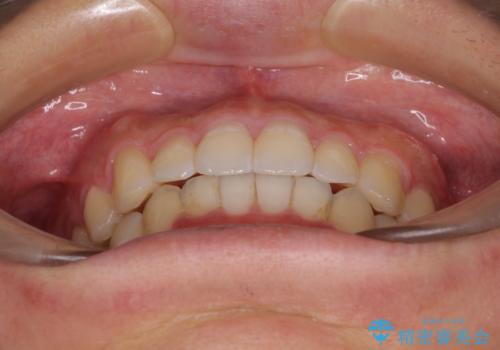

口が少し閉じにくい インビザラインによる非抜歯矯正

- 口元の突出感を治したいとのことで来院された患者様です。

上下顎ともにIPR(歯と歯の間を削る)と歯列全体の拡大によって口元が引っ込むように設計し、インビザラインにより治療を行うこととしました。

抜歯をして口元を下げなければならないほど出っ歯ではなかったため、少しずつ治療ゴールを変更しながら仕上げていきました。

気になっていた前歯の飛び出した印象は、最終的にはスッキリと引っ込み、大変満足していただきました。